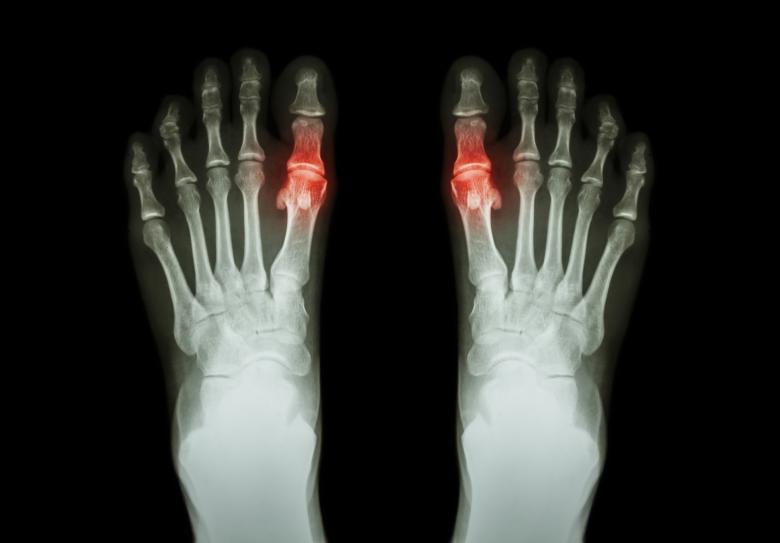

Pakostnice nejčastěji postihuje palec u nohy. „Postižené místo bývá horké, oteklé, velmi zarudlé a bolestivé. Kůže bývá napjatá a lesklá, čemuž se říká „fenomén zrcátka“. Nástup dnavého záchvatu může být doprovázen horečkou a dochází k němu nejčastěji v noci nebo časných ranních hodinách. Může trvat několik hodin nebo několik týdnů, obvykle trvá 7–14 dnů. Bolest i otok poté sice ustoupí, ale samotná nemoc v těle zůstává. Dnavý záchvat může proběhnout pouze jednou za život, ale také se může v budoucnu opakovat,” uvádí Lánová.

Po akutním záchvatu dny přichází takzvané interkritické období, kdy je pacient obvykle zcela bez obtíží. To může trvat měsíce, ale také déle než rok. U pacientů, kteří se neléčí a nedodržují dietní opatření, často dochází k nástupu chronické tofózní dny, která mívá charakter polyartritidy. „Může dojít ke vzniku dnavých tofů, nahromaděných krystalů solí kyseliny močové v kloubních i mimokloubních tkáních, typické je to na ušních boltcích. Při chronické tofózní dně dochází k destrukci kloubů,“ popisuje Lánová.